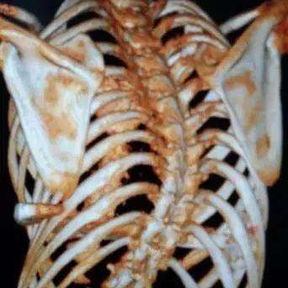

The patient is a 16-year-old male who has been diagnosed with pectus excavatum in childhood but experienced no discomfort in daily life. At the age of 15, he underwent Nuss procedure during which a bar was placed in his chest wall. However, the depression in his chest wall persisted after the surgery, and he even developed new severe deformities. As the deformities gradually worsened, the patient developed scoliosis, and his entire chest wall became completely distorted, eventually losing its basic shape. Later, the patient underwent another minimally invasive surgery for spontaneous pneumothorax, during which the surgeon ligated bilateral pulmonary bullae without treating the chest wall deformities. Ultimately, because of the severe deformities and breathing discomfort, the patient came to our hospital for treatment.

The patient was diagnosed with severe complex chest wall deformities accompanied by scoliosis. The heart was severely compressed and shifted to the left thoracic cavity.

We developed a personalized surgical plan for the patient. The operation first involved making incisions along the surgical scars on both sides of the chest wall to remove the bar inserted during the Nuss procedure. Then, a larger incision was made at the central scar on the anterior chest wall to fully expose the bone structure located at concave and convex areas of the chest wall. It was found that there were severe adhesions between the chest wall structure and the pericardium, with the heart being compressed into the left chest cavity.

​First, the adhesions were thoroughly released, and a portion of the protruding ribs and costal cartilage at the top of the protrusion was cut off. By lifting and pressing down, the chest wall was adjusted to its normal height. Second, three MatrixRIBs was used to replace the removed rib sections, and their curvature was carefully adjusted to closely resemble the normal curvature of the chest wall, thereby completing the reconstruction of the thoracic cage. Third, a bar was placed and flipped within the chest wall to elevate the most depressed part of the central chest wall. Lastly, two bars were placed on and secured to the bone surface of the lower half of the chest wall. The surgery achieved a satisfactory result, eliminating the deformities and restoring the chest wall to its normal shape.